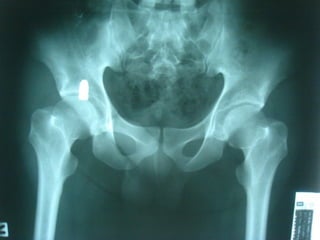

ชายไทยอายุ 21 ปี ถูกยิง 1 ครั้ง ที่ขา 2 ขา

ก่อนมาโรงพยาบาล 2 ชั่วโมง

ขาขา

ขวาขวา

ซ้ายซ้าย

Intraoperative Rx